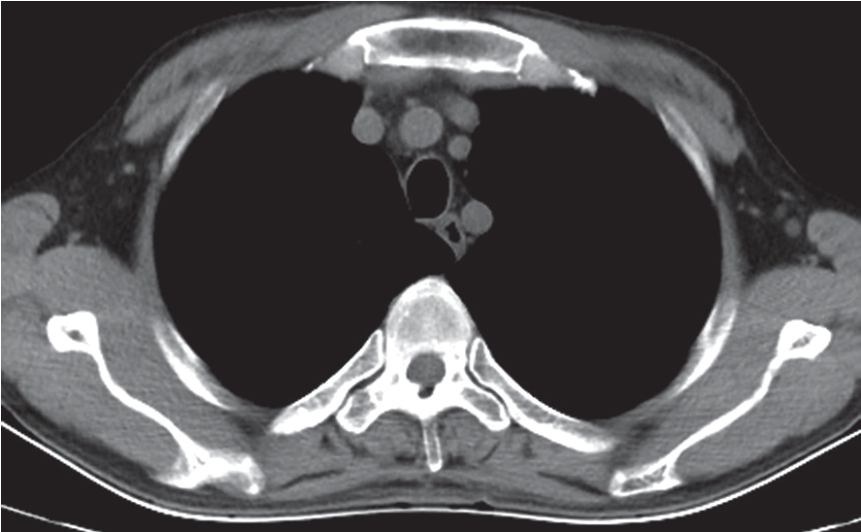

(2)胸椎CT平扫:经椎体平面可见椎体前的前纵韧带、胸主动脉,椎体后缘向前凹,两侧通过肋椎关节与肋骨相连,横突向后外侧展开,在横突末端有肋横关节、棘突,椎管内可见硬膜囊、脊髓等(图7-2-6)。经椎间盘平面横断面可见胸椎椎间盘,椎体后方两侧的椎间孔、横突、上下关节突、椎弓板、棘突、椎管及其内的脊髓等。

图7-2-6 胸椎CT平扫